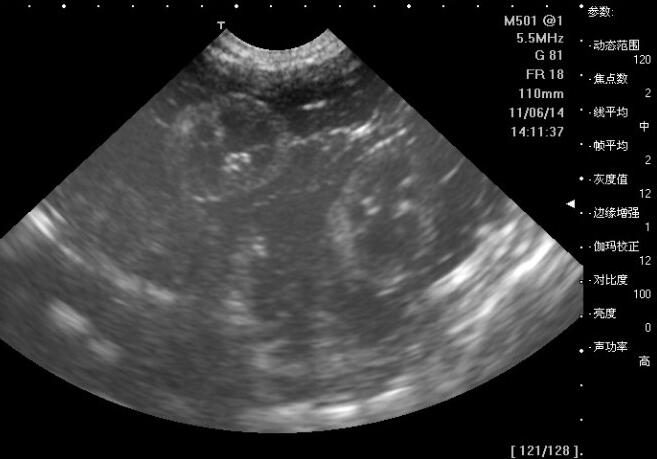

孕妇在怀孕的时候做十几次产前检查,B超一般都要做三五次,相信大家最熟悉不过了。通过B超,可以看出宝宝的生长发育、有没有畸形、胎盘的位置等情况。